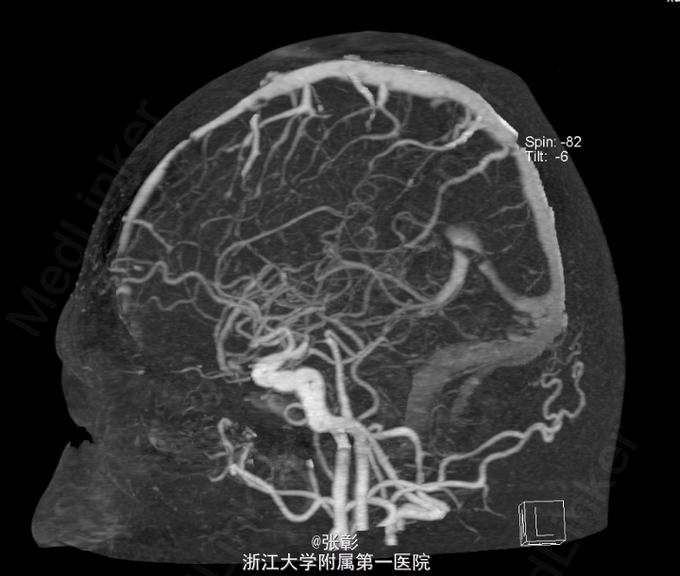

初步诊断:亚急性硬膜下血肿. 入院后行各项检查,(2015-06-24 11:40)血常规(五分类)(全血):白细胞计数9.2×10^9/L、血红蛋白139g/L、血小板计数245×10^9/L、(2015-06-24 10:57)电解质全套(血清):白蛋白45.9g/L、钾3.87mmol/L、钠138.0mmol/L、肌酐79μmol/L、甘油三酯1.89mmol/L↑、C-反应蛋白7.1mg/L、(2015-06-24 14:25)肿瘤标记物全套(男)(血清):癌胚抗原1.2ng/mL、甲胎蛋白1.9ng/mL、癌抗原1996.0U/mL。(2015-06-23 19:42)行CT(头部)检查提示:脑动脉CTA检查未见异常CT征象。右侧额颞顶部硬膜下血肿。进一步行脑血管造影:脑血管造影未见明显异常。给予对症支持治疗。